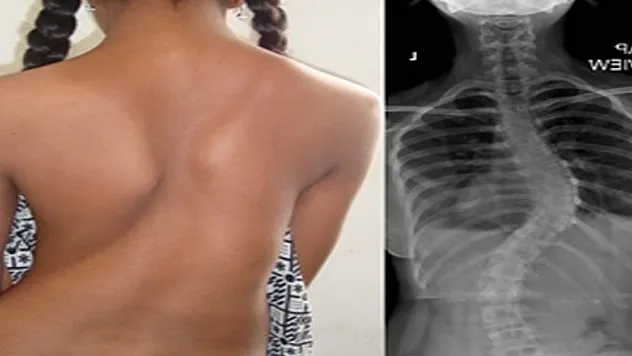

Türkiye'de 2,5 milyon 'skolyoz' hastası var